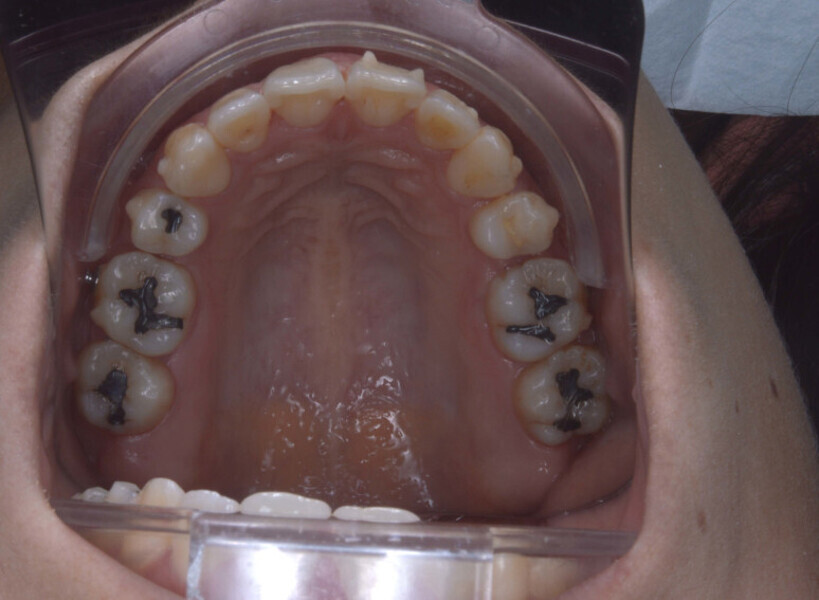

A 35-year-old female patient presented with crowding, muscle and joint pain, and headaches upon awakening. Examination found a skeletal Class I with crowding and bimaxillary protrusion. Facial examination showed a convex profile with protruded lips and a square face shape, intensified on smiling (Figs. 1–4). She reported bruxism, and bilateral masseteric hypertrophy was observed, but there was no alteration of the temporomandibular joints.

Before the aligner treatment began, the maxillary and mandibular second premolars were extracted to create space. With orthodontic treatment, distalisation of the anterior teeth was achieved by employing maximum mandibular anchorage and moderate maxillary anchorage (Figs. 5–7). At the end of the treatment, a stable bilateral Class I occlusion had been achieved, as well as normal inclination and retrusion of the anterior teeth, consequently improving the profile (Figs. 8–10).